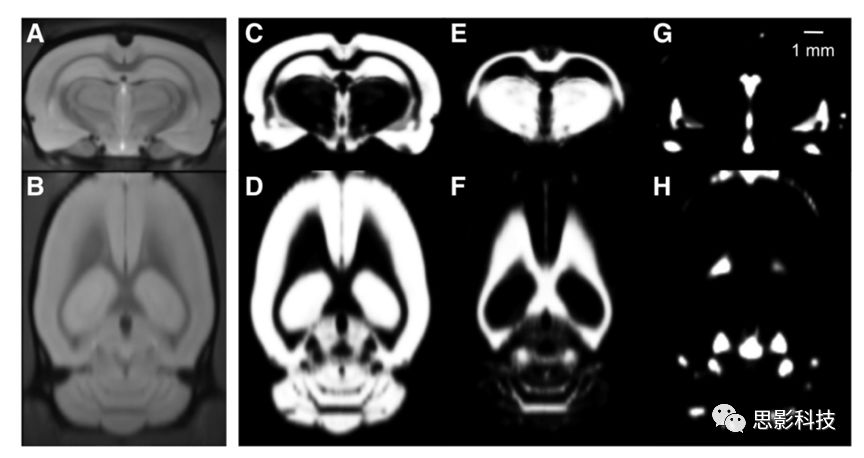

1、基于體素的形態(tài)學(xué)分析(VBM)

借助FSL/VBM8等工具包對T1像進(jìn)行分割、配準(zhǔn)并計(jì)算灰白質(zhì)體積密度。

灰白質(zhì)分析圖例